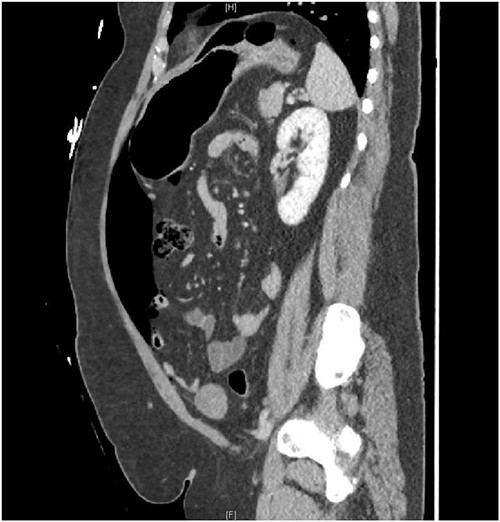

A 30-year-old female presented to the emergency department due to severe abdominal pain that had started suddenly 5 h prior to arrival. Symptoms began after eating dinner. She had no prior medical history or prior abdominal surgeries, however had recently been taking an increased amount of NSAIDs due to a tooth infection. On presentation, she was tachycardic with a heart rate in the 120 s and had a leukocytosis of 14.9. She was otherwise hemodynamically stable and afebrile. A CT abdomen/pelvis with IV (no oral) contrast demonstrated a moderate amount of pneumoperitoneum without a definite source (Figs 1 and 2). She was taken for exploratory laparotomy where full examination of the gastroesophogeal junction, stomach, duodenum, ascending and descending colon, and pelvic organs were examined in detail without any findings of perforated viscus. An intraoperative endoscopy was then performed and was normal, as well as intraoperative colonoscopy. A temporary abdominal closure device was placed, and she was taken to the intensive care unit (ICU) for continued monitoring. Post-operatively she underwent further testing including a CT abdomen/pelvis with IV and oral contrast followed by gastrografin enema both with negative findings. She returned to the operating room for abdominal closure on post-operative day 2 that required an anterior component separation with onlay mesh given significant loss of domain. At this time, her leukocytosis had also resolved. The patient was tolerating a regular diet 3 days after abdominal closure (5 days after index procedure) and discharged home on post-operative day 6.